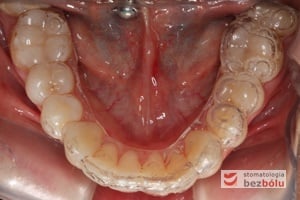

Pozycjonery to system przezroczystych nakładek precyzyjnie dopasowanych do łuków zębowych pacjenta, które przesuwają zęby w odpowiednio zaplanowane i wyznaczone przez lekarza ortodontę miejsca. Stanowią one alternatywne rozwiązanie dla aparatów stałych i ruchomych, jakkolwiek zakres wskazań do ich stosowania jest mocno ograniczony w porównaniu z aparatami stałymi. Są wykonywane indywidualnie dla każdego pacjenta, przez wykwalifikowanego technika dentystycznego.

- Natłoczenie szyny metodą termoformingu w zależności od metody leczenia dokonujemy wyboru płytki o odpowiedniej grubości (1,0 standardowo ). Materiałem, z którego wykonywane są nakładki jest erkodur.

- Oddanie pacjentowi gotowych nakładek i poinstruowanie o posługiwaniu się nakładkami oraz ich pielęgnacji